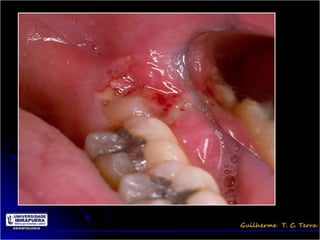

Pericoronarite

• Infecção dos tecidos moles (Opérculo)

que recobrem a coroa de um dente

incluso

• A dificuldade de higienização sob o

opérculo

Tratamento da Pericoronarite

• Regredir a infecção antes da cirurgia

– Remissão dos sinais e sintomas

• A exodontia com dentes associados a

pericoronarites pode disseminar a infecção

• Remoção do opérculo???